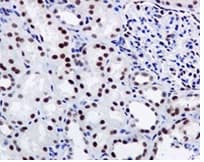

Anti-FTO antibody [EPR6895] - BSA and Azide free(ab242390)

Rabbit Recombinant Monoclonal FTO antibody. Carrier free. Suitable for IHC-P, WB and reacts with Human samples.

Applications Flow Cyt, ICC/IF, IHC-P, IP, WB

Species Reactivity Human, Mouse, Rat